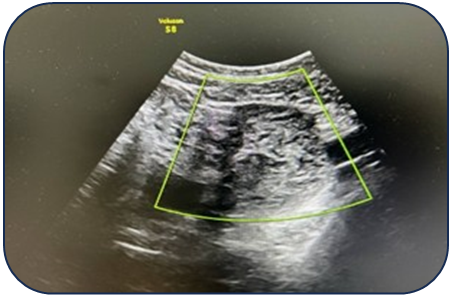

Case 1: A 17-year-old female presented with acute pain. Ultrasound revealed a 95 mm complex left ovarian cyst with no Doppler flow (Fig. 1). Emergency laparoscopy confirmed a 720-degree torsion. Detorsion and cystectomy were performed. Intraoperative findings are shown in Fig. 2, Fig. 3, and Fig. 4. Histopathology reported a serous cystadenoma. Postoperative ultrasound on day 5 confirmed a viable ovary (Fig. 5). | Figure 1. Ultrasound findings of a left ovarian cyst with torsion |